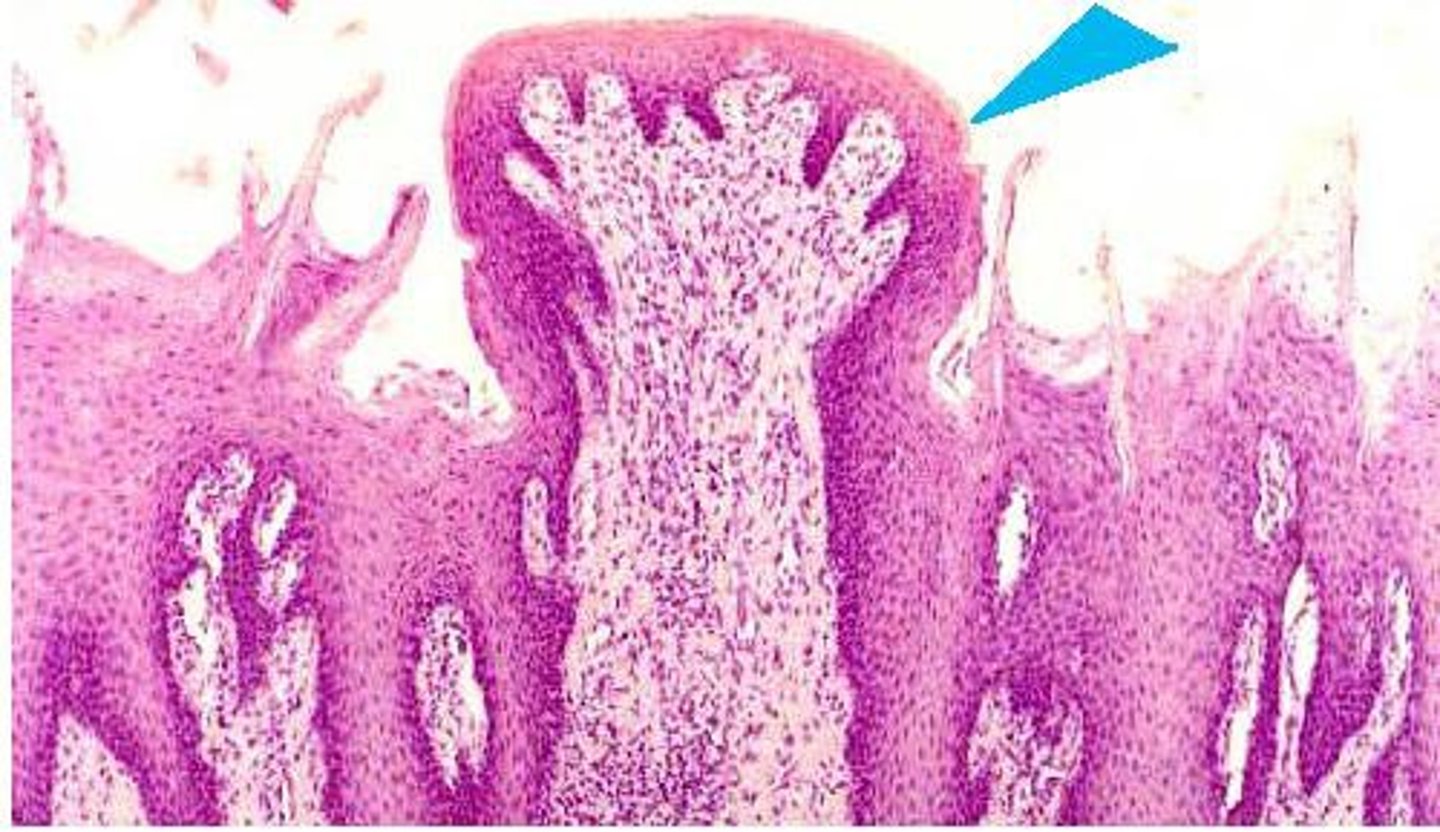

Papillae

Structures on the tongue that contain taste buds

Vallate papillae

Posterior, arranged in the form of a V

Fungiform papilla

located allover tongue, rounded

filiform papillae

Only touch receptors